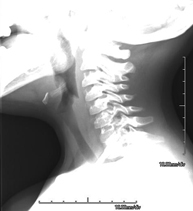

Técnica mediante la cual, utilizando rayos X, se obtienen imágenes del cavum para su estudio. Indicaciones: dificultad respiratoria, anginas de repetición en lactantes y niños. - RX Columna cervical

Técnica mediante la cual, utilizando rayos X, se obtienen imágenes de la columna cervical para su estudio. Indicaciones: traumatismo, contractura cervical, dolor articular. - RX Huesos propios nasales